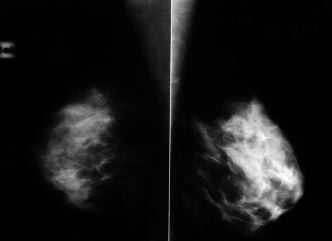

Paciente de 32 años con hallazgo de una adenopatía axilar izquierda de un mes de evolución, sin nódulo mamario palpable. Las mamografías no evidenciaban lesión mamaria sospechosa (Figs. 1 y 2). La adenopatía fue puncionada, siendo positiva para malignidad y sugestiva de neoplasia epitelial de origen glandular. Se realizó estudio de extensión de carcinoma de mama sin hallazgos de interés. Decidimos realizar una RNM mamaria, observándose un área de hipercaptación de contraste en el cuadrante superoexterno de la mama izquierda, sin que se pudiera precisar si correspondía a cambios inflamatorios, mastopáticos o neoplásicos.

Figura 1. Mamografía bilateral proyección oblicua.